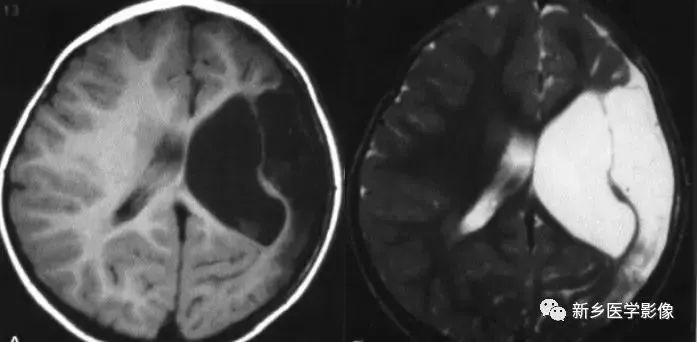

外伤后脑萎缩,感染后脑萎缩,脑梗死后脑萎缩CT可见扩大的脑室部分附近的脑实质呈片状低密度灶MR:T1WI呈低信号,T2WI呈高信号。同时脑沟及蛛网膜下腔增宽。

2.侧脑室神经上皮囊肿

通常位于侧脑室三角区,囊壁薄,通常显示不清由于囊内含脑脊液,所以CT及MR都表现为脑脊液信号。